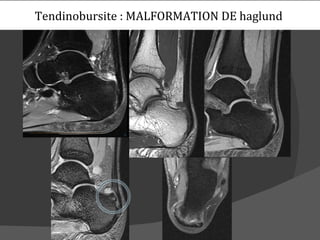

Tendinobursite : MALFORMATION DE haglund